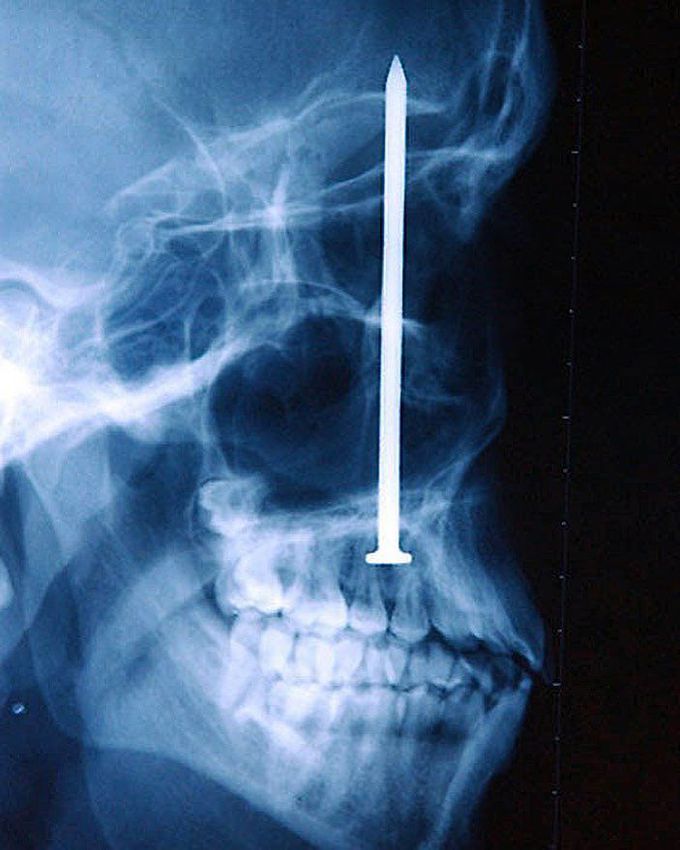

This guy nailed it - literally!!!The patient was messing around with a nail gun too close to his face, sending it straight up into his face. According to him, he didnโt even realize he had been shot until 6 days later when the four-inch nail was discovered, which is pretty hard to comprehend.

This X-ray confuses me. The nail gun has breached the cranial fossa, surpassed the eyes, penetrated his maxillary bone and lies between both his eyes. How has he not noticed. He must've had some sort of neuronal deficit, he definitely had some bleeding and I'm certain there was pain. These cases genuinely amaze me ๐ฎ๐ฎ